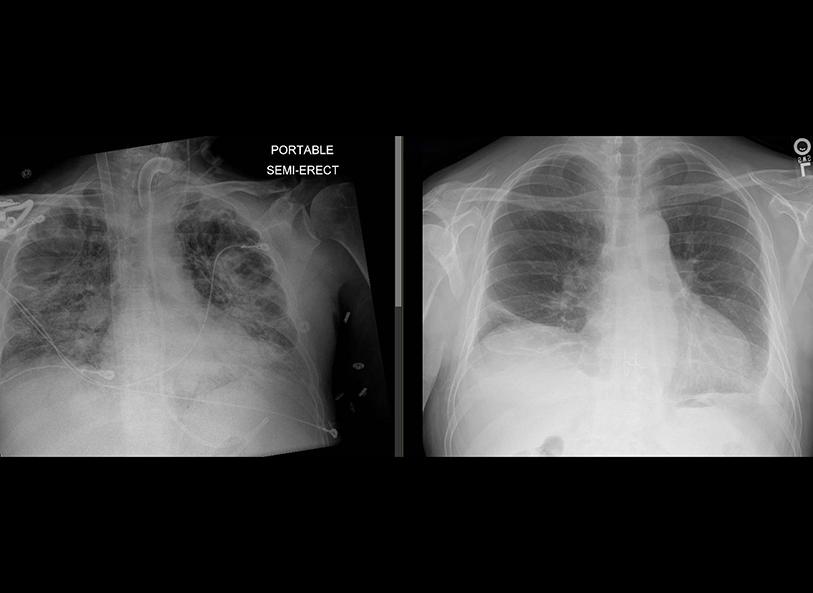

• Superior imaging | An X-ray or CT scan is traditionally used to help pinpoint the location of a tumor prior to radiation therapy. An MRI provides a more detailed image and can help doctors distinguish between soft tissue and a tumor. According to Paul Read, MD, medical director of the Department of Radiation Oncology, the more clearly we can see the margins of the tumor, the better our chances of avoiding normal tissue during treatment. The result: fewer side effects.